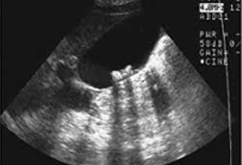

방사선이 통과할 수 없는 색소성 담석은 단순 복부 촬영에서 보일 수 있지만 콜레스테롤 담석은 찾을수 없습니다. 담도 내에 공기가 보이는 경우 세균 감염 또는 담관-장의 루를 의심할 수 있으며 담낭의 석회화는 만성 담낭염을 의미합니다. 초음파 검사는 담석의 진단에 가장 좋은 검사법으로서 진단율은 95%에 이릅니다. 불편없이 간단히 검사할수 있는 장점이 있습니다. 경구 담낭조영술도 담석 진단법 중 하나인데 만성 담낭염으로 담낭 기능이 손상된 경우, 담낭관이 폐쇄된 경우, 간질환이 있는 경우 담낭이 비정상적으로 보이지 않게 됩니다.

담낭 초음파사진 이미지